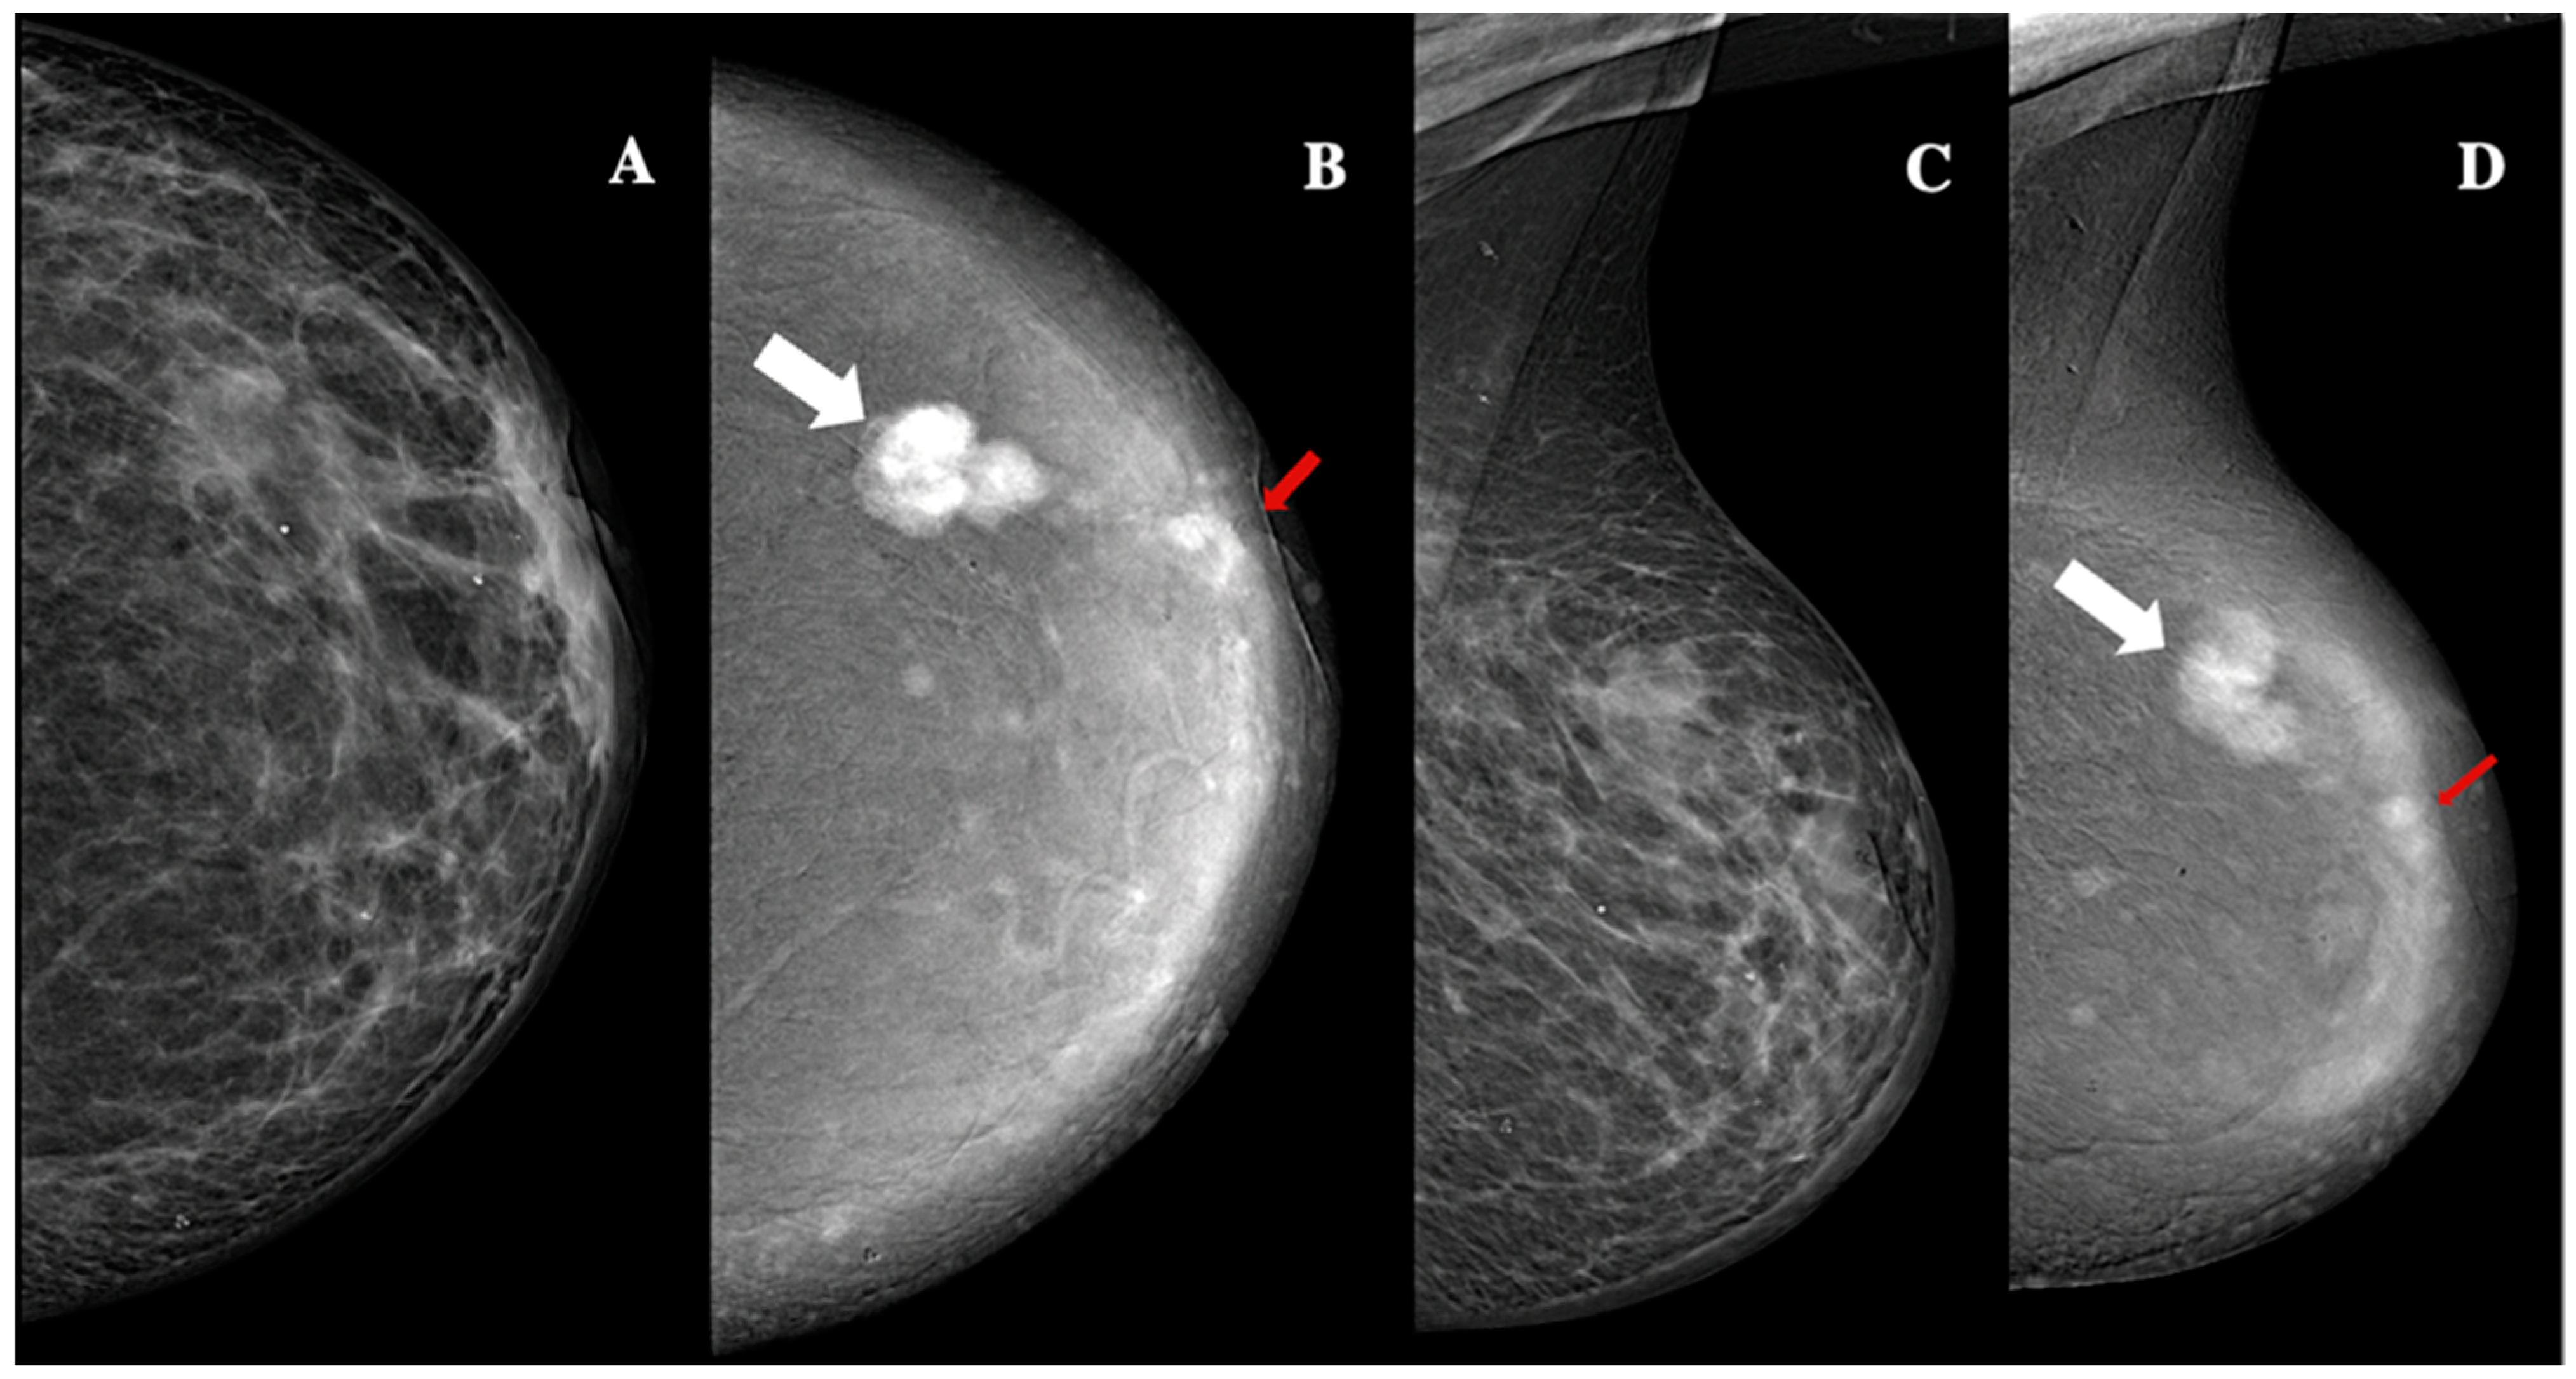

| Microcalcifications | Present (n, %)/absent (n, %) | 11 (22%)/39 (78%) |

| Architectural distorsion | Present (n, %)/absent (n, %) | 34 (68%)/16 (32%) |

| Lesion shape | Oval (n, %)/round (n, %)/irregular (n,%) | 31 (62%)/9 (18%)/10 (20%) |

| Lesion margins | NC (n, %)/C (n, %) | 7 (14%)/43 (86%) |

| Lesion internal enhancement | Homogeneous (n, %) | 8 (16%) |

| Heterogeneous (n, %) | 37 (74%) | |

| Rim enhancement (n, %) | 5 (10%) | |

| Lesion enhancement conspicuity | Low (n, %) | 25 (50%) |

| Moderate (n, %) | 10 (20%) | |

| High (n, %) | 15 (30%) | |